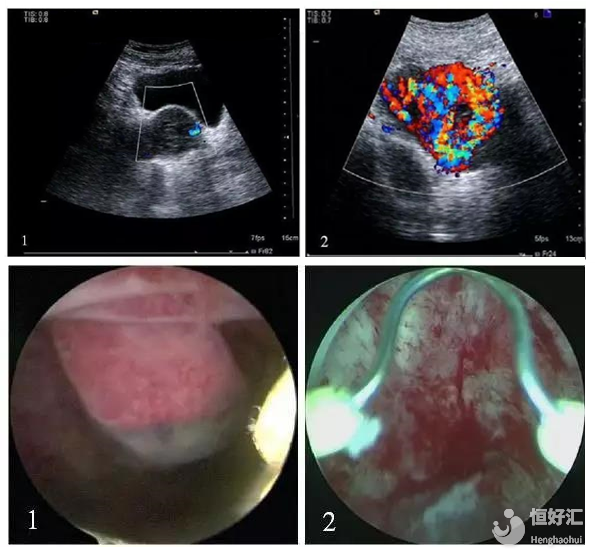

超聲下III型CSP 宮腔鏡下CSP影像

1、漿膜層明顯外突,切口處未見明顯正常肌層。 1、宮腔鏡下可見子宮前壁剖宮產瘢痕部位孕囊。

2、CDFI:混合團塊內可見豐富的動靜脈血流信號。 2、宮腔鏡下電極電凝止血。

結合以上的表格,就請再看看表下的圖片,上邊的兩張圖是超聲下的情形,下邊的的兩張圖是宮腔鏡下的情形,也就是“上左下右”哦。其實,CSP是可以發生子宮破裂、失血性休克、致命性大出血、瘢痕部位破裂等情況,這屬于異位妊娠的一種,就好比就是人們常說的宮外孕,且兇險程度可謂是旗鼓相當,絲毫不可懈怠。